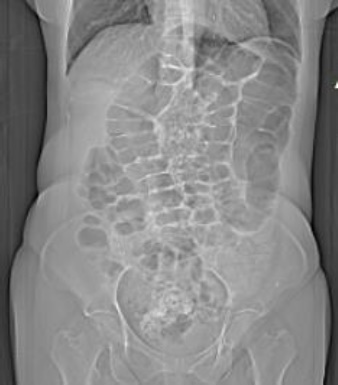

Rx de abdomen simple de pie se observó marco colonico redundante y engrosamiento de la pared colónica a nivel de colon descendente y colon sigmoide (Figura 2).